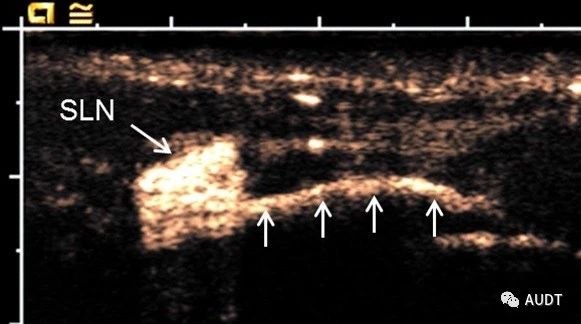

618972069d2e6a7614b451a689b27e17.jpg

图21.淋巴结超声造影:猪黑色素瘤周围皮下注射Sonazoid后,显示前哨淋巴结(SLN)和引流淋巴通道(箭头)。